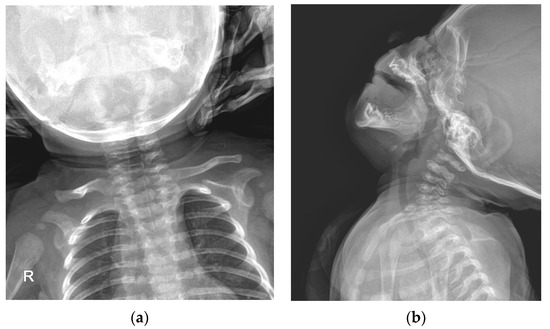

A simple radiographic evaluation was performed to identify any other related complications. To rule out vertebral anomalies, particularly high cervical vertebrae deformations—which could be a cause of congenital torticollis—we examined the cervical spine [9]. The cervical spine simple radiograph was obtained in the anteroposterior view and lateral-extension view (Figure 3). No bony abnormalities or airway obstructions were detected. Whole-spine simple radiography revealed mild right-side thoracolumbar scoliosis (Figure 4). The Cobb angle of the thoracolumbar curve was 12 degrees. Both scanography and pelvic simple radiography revealed no abnormalities in the lower limb and hip regions.

Figure 3. Cervical spine simple radiograph: (a) Anteroposterior view of the cervical spine; (b) Lateral-extension view of the cervical spine.